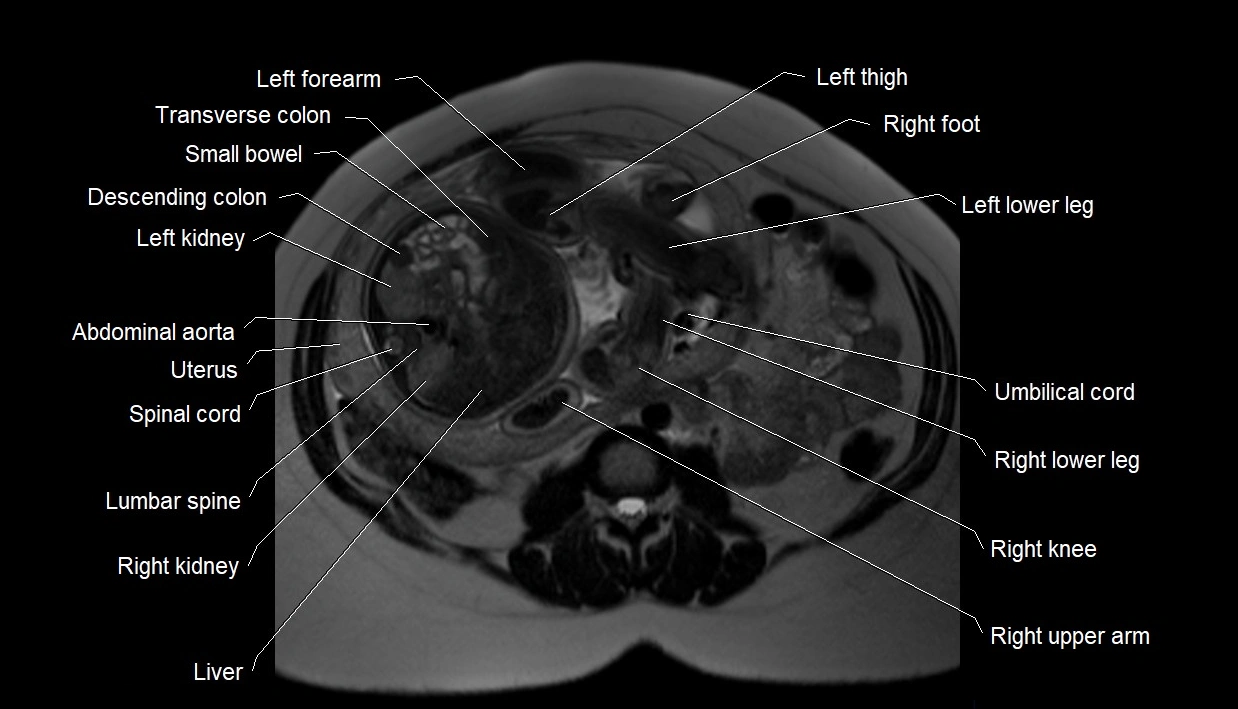

MRI Appearance

T2 HASTE (T2 GRE):

• Amniotic fluid shows very bright hyperintense signal

• Provides natural contrast against fetus and placenta

• Small particles (vernix) may appear as scattered hypointense foci within bright fluid

T1 GRE:

• Amniotic fluid shows low signal intensity (dark)

• Hemorrhage, infection, or proteinaceous content may cause focal or diffuse high signal intensity

MRI image

image